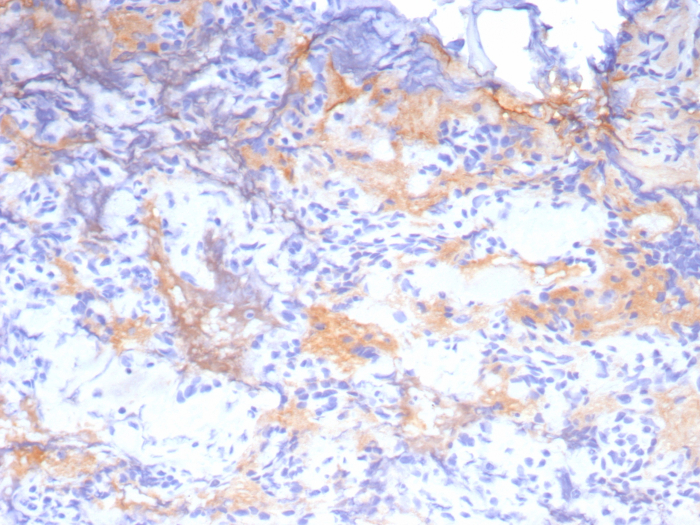

Formalin-fixed, paraffin-embedded human placenta stained with Growth Hormone antibody (GH/8215R). Inset: PBS instead of primary antibody; secondary only negative control.